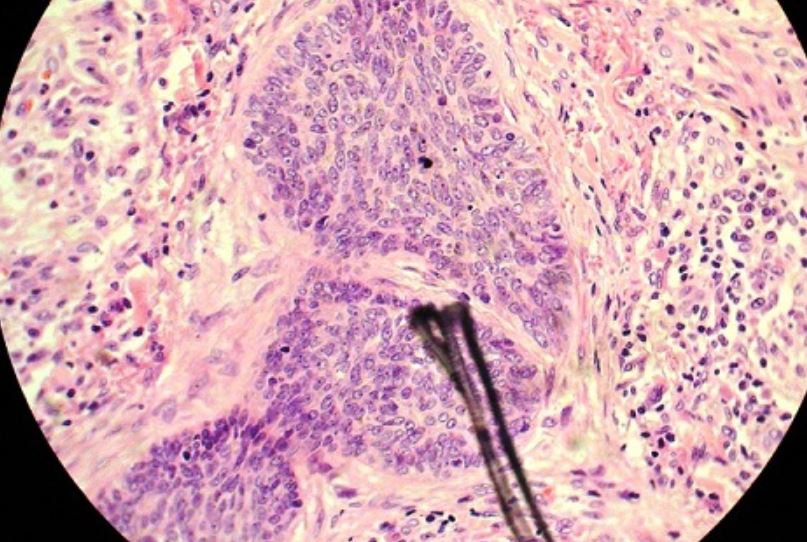

- Phương pháp liqui prep là xét nghiệm có giá trị cao giúp phát hiện phụ nữ mắc ung thư cổ tử cung ở giai đoạn sớm lên đến 70%. Đây là bước cải tiến vượt bậc giúp làm tăng độ nhạy và độ đặc hiệu trong việc phát hiện các tế bào tiền ung thư, đặc biệt là ung thư tế bào biểu mô tuyến.

Hình ảnh ung thư tế bào biểu mô tuyến